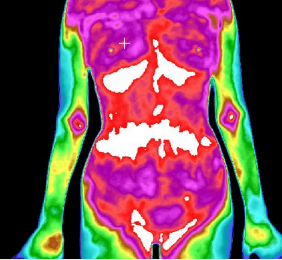

3、推测未来可能出现的疾病

肠道炎性反应

胆囊炎性反应